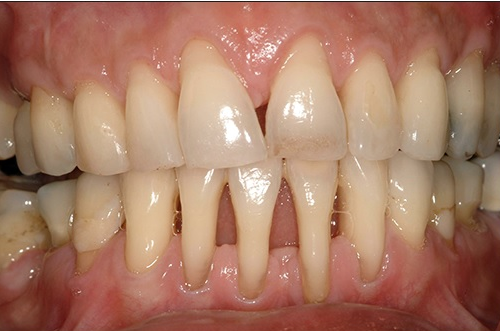

A periodontite agressiva juvenil é uma doença gengival séria que afeta jovens. Ela causa destruição rápida do osso e dos tecidos que sustentam os dentes. O diagnóstico precoce é crucial para evitar a perda dentária.

A regeneração tecidual entra em cena depois que a inflamação está sob controle. O objetivo é recuperar os tecidos que foram danificados pela doença. Isso pode envolver procedimentos como raspagem e alisamento radicular para limpar as bolsas periodontais. Em casos mais avançados, a gente pode pensar em enxertos ósseos ou de gengiva, tudo para ajudar o corpo a se reconstruir.

Vamos falar sério agora sobre periodontite agressiva juvenil. Se você ou alguém que você conhece está lidando com isso, sabe que é um assunto delicado. Basicamente, quando a doença periodontal avança e a inflamação já causou perdas ósseas significativas, a cirurgia pode ser o caminho. É aquela situação em que a limpeza profunda que fazemos não consegue mais alcançar as bactérias mais problemáticas.

Eu já vi casos onde a gengiva se retrai muito, deixando a raiz do dente exposta. Isso não é só questão estética, viu? Aumenta a sensibilidade e o risco de cáries nessa área. A cirurgia periodontal entra para tentar recuperar o suporte dos dentes, removendo as bolsas periodontais e, em alguns casos, até regenerando o osso perdido. É um procedimento para quando outras abordagens não foram suficientes, entende?

O objetivo principal da cirurgia é tornar a área mais fácil de limpar, removendo as bactérias que se escondem nas bolsas profundas. Isso ajuda a parar a progressão da doença e a salvar os dentes. É um passo importante para quem busca um tratamento mais completo contra a periodontite agressiva juvenil, pensando na saúde bucal a longo prazo.